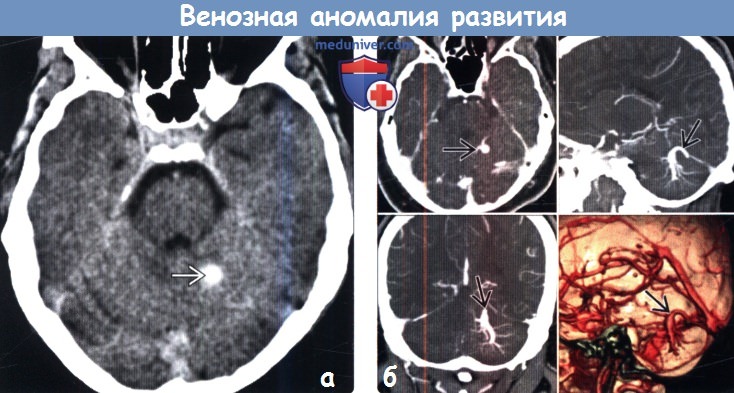

Мр картина венозной ангиомы левой гемисферы мозжечка - 96 фото